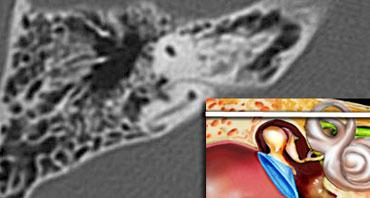

Hang chũm

Ở mức này, hang chũm được thấy bao quanh bởi các tế bào khí chũm nhỏ hơn, nằm ngay bên ngoài các ống bán khuyên trên.

Ba ống bán khuyên nằm vuông góc với nhau để cảm nhận các chuyển động gia tốc và giảm tốc trong mỗi trong 3 mặt phẳng không gian.

Vị trí tĩnh của đầu được cảm nhận bởi tiền đình, nơi chứa các tế bào lông cảm nhận vị trí.

Các tư thế đầu khác nhau tạo ra các hiệu ứng trọng lực khác nhau bởi các hạt canxi carbonat nhỏ (otolith) lên các tế bào lông này.